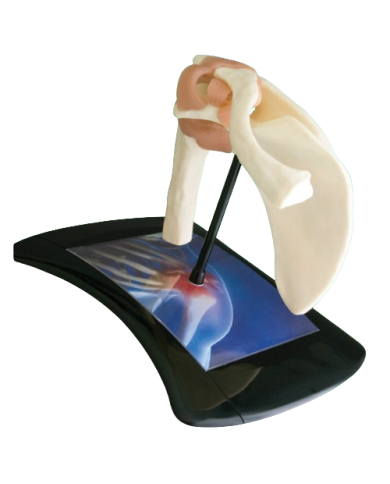

Modello anatomico PER FORNITURE CASE FARMACEUTICHE

Modello anatomico PER FORNITURE CASE FARMACEUTICHE

Modello anatomico PER FORNITURE CASE FARMACEUTICHE

Modello anatomico PER FORNITURE CASE FARMACEUTICHE

Modello anatomico PER FORNITURE CASE FARMACEUTICHE

Modello anatomico PER FORNITURE CASE FARMACEUTICHE

Modello anatomico PER FORNITURE CASE FARMACEUTICHE

Modello anatomico PER FORNITURE CASE FARMACEUTICHE

Modello anatomico PER FORNITURE CASE FARMACEUTICHE

Modello anatomico PER FORNITURE CASE FARMACEUTICHE

Modello anatomico PER FORNITURE CASE FARMACEUTICHE

Modello anatomico PER FORNITURE CASE FARMACEUTICHE

Modello anatomico PER FORNITURE CASE FARMACEUTICHE

Modello anatomico PER FORNITURE CASE FARMACEUTICHE

Modello anatomico PER FORNITURE CASE FARMACEUTICHE

Modello anatomico PER FORNITURE CASE FARMACEUTICHE

Modello anatomico PER FORNITURE CASE FARMACEUTICHE

Modello anatomico PER FORNITURE CASE FARMACEUTICHE

Modello anatomico PER FORNITURE CASE FARMACEUTICHE

Modello anatomico PER FORNITURE CASE FARMACEUTICHE

Modello anatomico PER FORNITURE CASE FARMACEUTICHE

Modello anatomico PER FORNITURE CASE FARMACEUTICHE